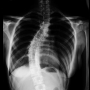

| 5009 |

흉추부 X-ray 사진

1 |

정주연 | 2016.09.16 | 2598 |